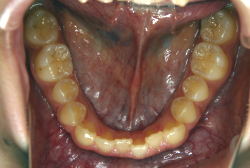

混合歯列期から治療開始した側方拡大による非抜歯症例

「配列の凸凹を治したい」という主訴で来院したケースです。診断の結果、永久歯がすべて生えそろうと、かなり厳しい叢生(歯並びの凸凹のことです)になる可能性が高いと判明しました。原因としては特に上の顎の骨が小さいため、歯を収容する容量不足になっていると診断しました。このケースの場合は、成長発育期に治療開始しますので、顎の骨を土台ごと大きくすることが可能です。

そこで、まず急速拡大装置を使用して上顎骨の拡大を行い、上顎骨の容量が拡大したことを確認後、マルチブラケット装置を使って全体の修正をする、と言う二段階の作戦をとることになりました。

この時期に使う急速拡大装置は、適切な診断に基づいて正しく使用することで確実に骨を大きくすることができます。拡大することで隙間が確保できるので、永久歯の抜歯を避けることができます。

急速拡大装置を1日1回装置の中央にある拡大ネジを、ご自身で回して頂くことで25日間くらいかけて、6mmほど拡大しました。拡大後は、上顎の前歯の隙間が広がっていることがお分かりいただけると思うのですが、土台の骨ごと広がるのでこのような隙間ができます。その後1年半くらいマルチブラケット装置を使用して、全体の修正を行いました。

結局、歯の本数を減らすことなく、すべてご自分の歯を残して正しい配列にすることができました。このケースの場合、2009年10月より拡大と経過観察を行い、2012年3月より1年2ヶ月マルチブラケット装置を装着、2013年5月に治療を終了しました。2段階で行う治療としては短期間で終了しているケースと思います。